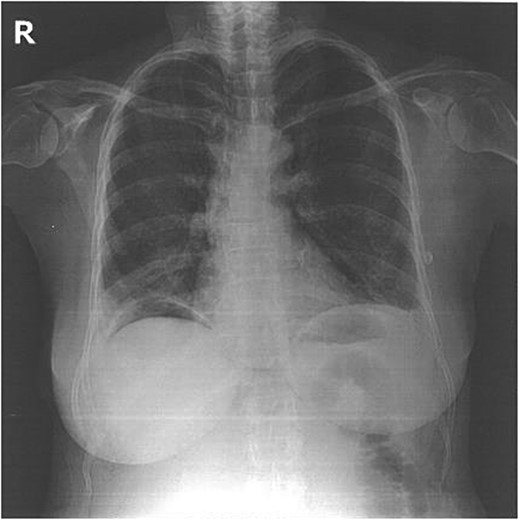

Laboratory investigations were within normal limits. The ECG was unremarkable. Chest X-ray showed the presence of a metallic image ∼5–6 cm long, located in the right hemithorax. There was a large hemothorax but no pneumothorax (Fig. 1). The investigation was complemented by a chest computed tomography (CT) that confirmed the presence of a metallic wire in the right pleural space.

She was placed in a left lateral decubitus position and a posterolateral thoracotomy in the fifth right intercostal space was used. The wire was removed without complications. Surprisingly, no injury was noted to any intervening abdominal structure intra-operatively. As a precaution, a 28-F chest tube was placed. There was no air leak or bleeding postoperatively and the tube was removed on the second postoperative day. The postoperative outcome was favorable and the patient was discharged on postoperative Day 4 with a normal chest radiogram (Fig. 2).